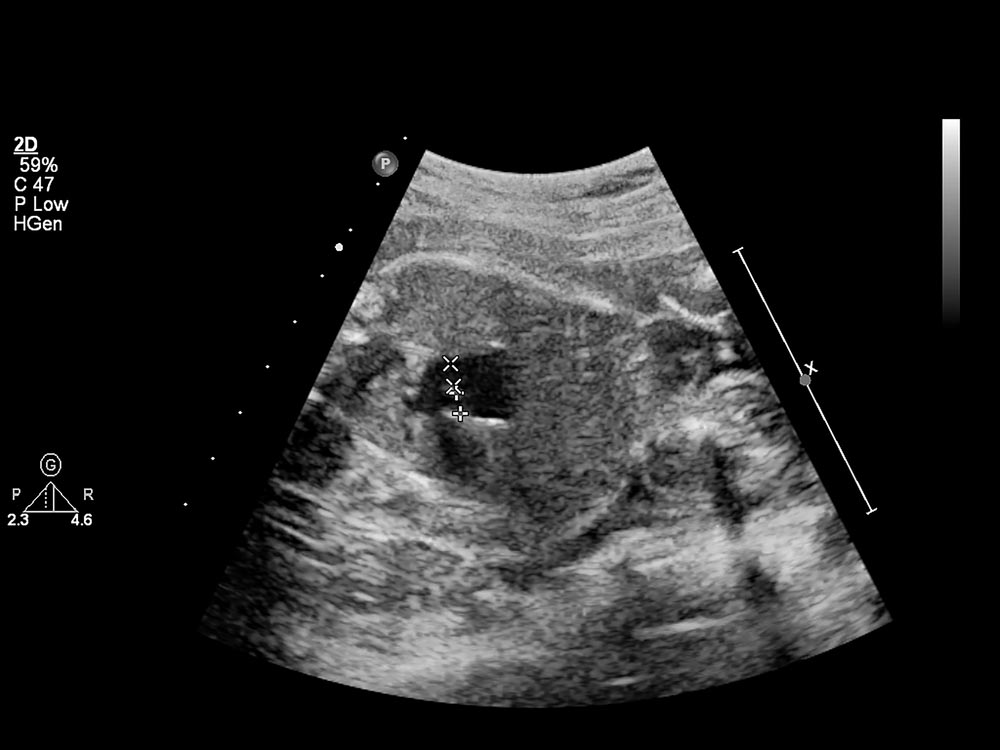

Pour que la mesure soit validée, l’embryon doit avoir une taille spécifique. Le médecin mesure d’abord la Longueur Crânio-Caudale (LCC), soit la distance tête-fesses.

La LCC de l’embryon doit être strictement comprise entre 45 et 84 mm. De plus, la mesure doit être faite exclusivement sur une coupe sagittale stricte de l’embryon (de profil parfait), avec la tête en position neutre. Si le fœtus est recroquevillé ou a la tête trop en extension, la mesure de la nuque sera faussée. L’échographiste devra alors patienter et faire bouger la mère.

Il n’y a pas une seule bonne mesure, mais une courbe de croissance. Une épaisseur de nuque est évaluée par rapport à la LCC du fœtus le jour de l’examen.

Selon les données médicales, une clarté nucale normale mesure environ 2 mm ou moins à la 11ème semaine. À la 13ème semaine et 6 jours, elle grandit proportionnellement au fœtus et devrait mesurer aux alentours de 2,8 mm au maximum pour rester dans la moyenne stricte.

Comment la clarté nucale est-elle mesurée par le médecin ?

L’échographiste doit obtenir une coupe sagittale stricte (un profil parfait du bébé, tête non fléchie). Il place ses curseurs à l’endroit le plus large de l’espace liquidien situé entre la peau et les tissus sous-cutanés de la nuque.